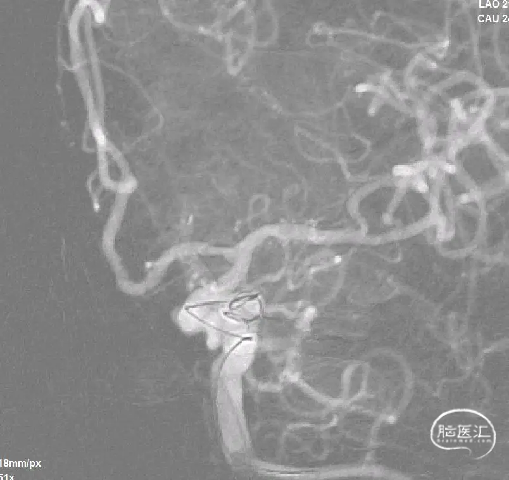

术前影像

栓塞过程

Tethys®中间导引导管到达C2段远端,上行第一根栓塞微导管,至动脉瘤瘤颈口,并填入一枚Jasper®SS弹簧圈;上行第二根栓塞微导管至动脉瘤子囊,并填入一枚Jasper®SS弹簧圈,再填入多枚Jasper®SS弹簧圈。